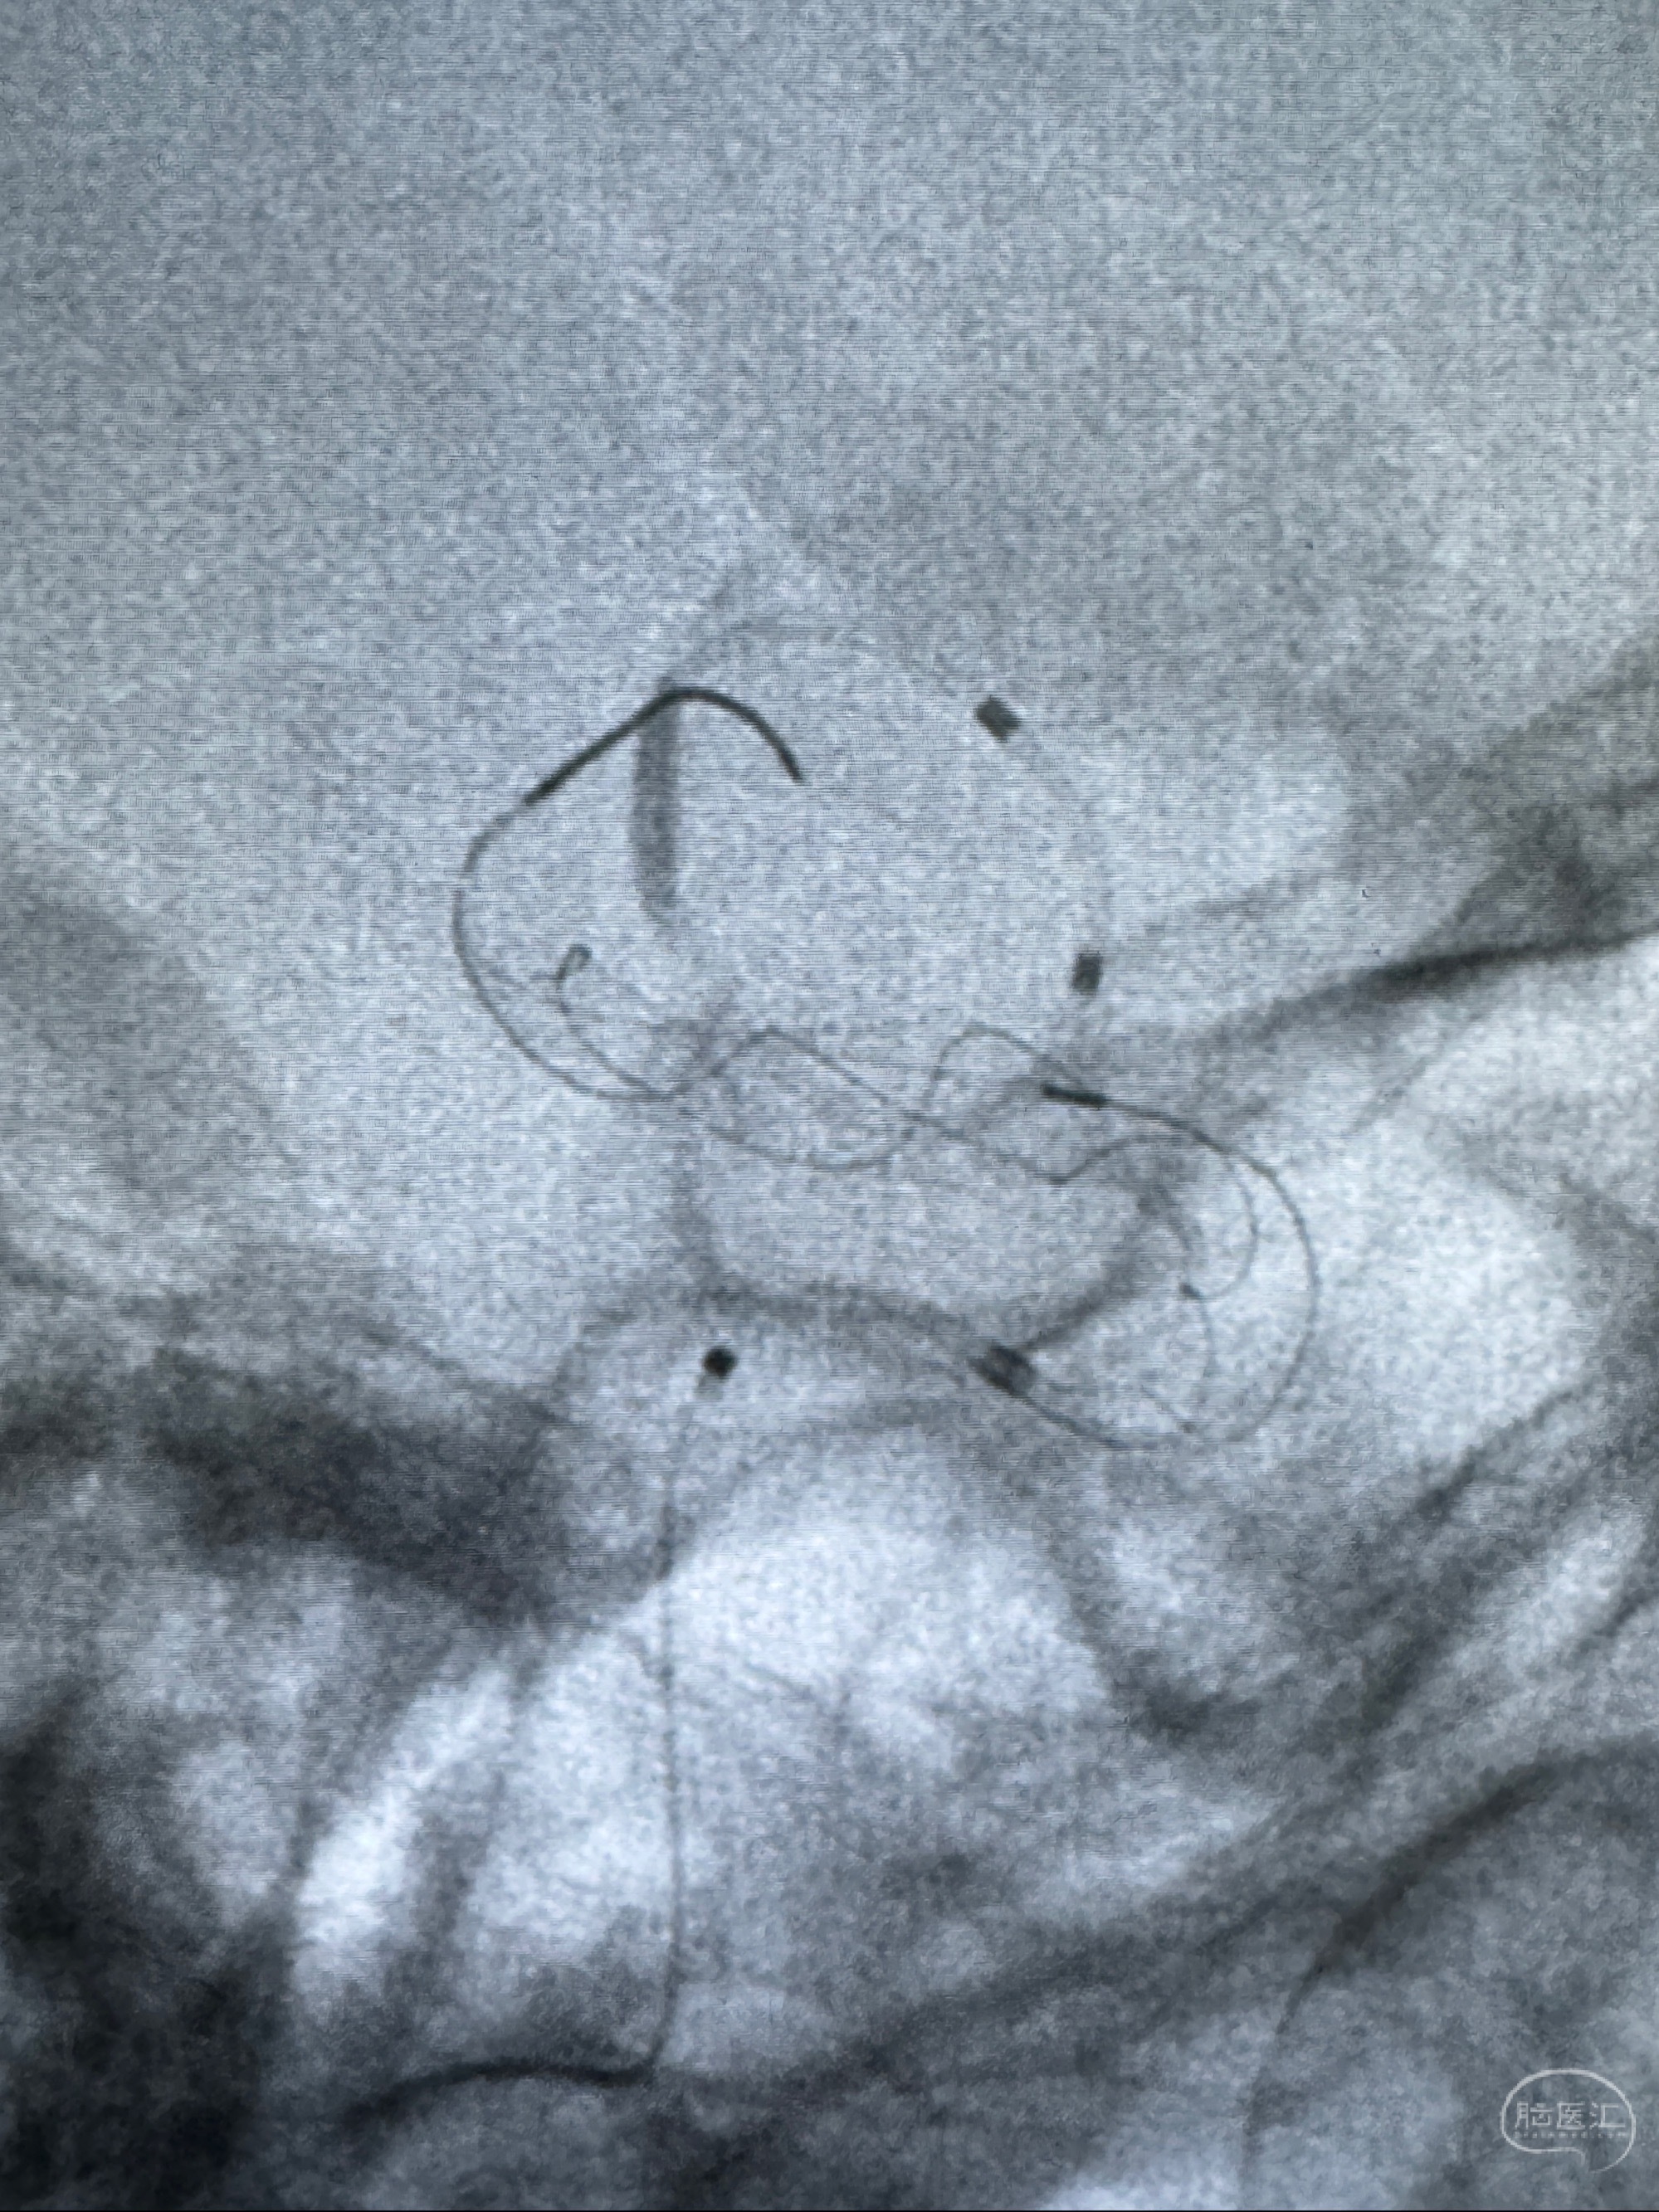

透视可见红圈部分为支架导管的头端

手推冒烟显示支架位置及展开情况,箭头为支架导管的位置

尝试回收支架失败,只能考虑释放支架了

逐帧图像展示歪着脖子释放支架,旁边吩咐助手手机摄影、拍照留像(透视机不能留影像)

接下的视频为释放支架的过程及试图确认支架与血管的关系